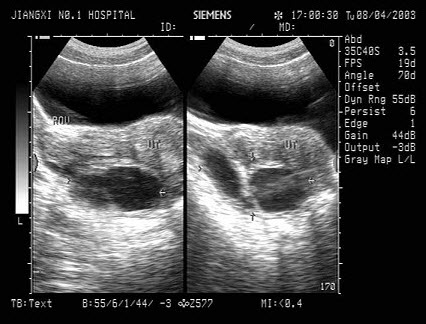

某患者脾脏声像图表现如图,诊断为()

A.正常脾脏

B.脾大

C.脾破裂

D.脾梗死

E.以上都不是